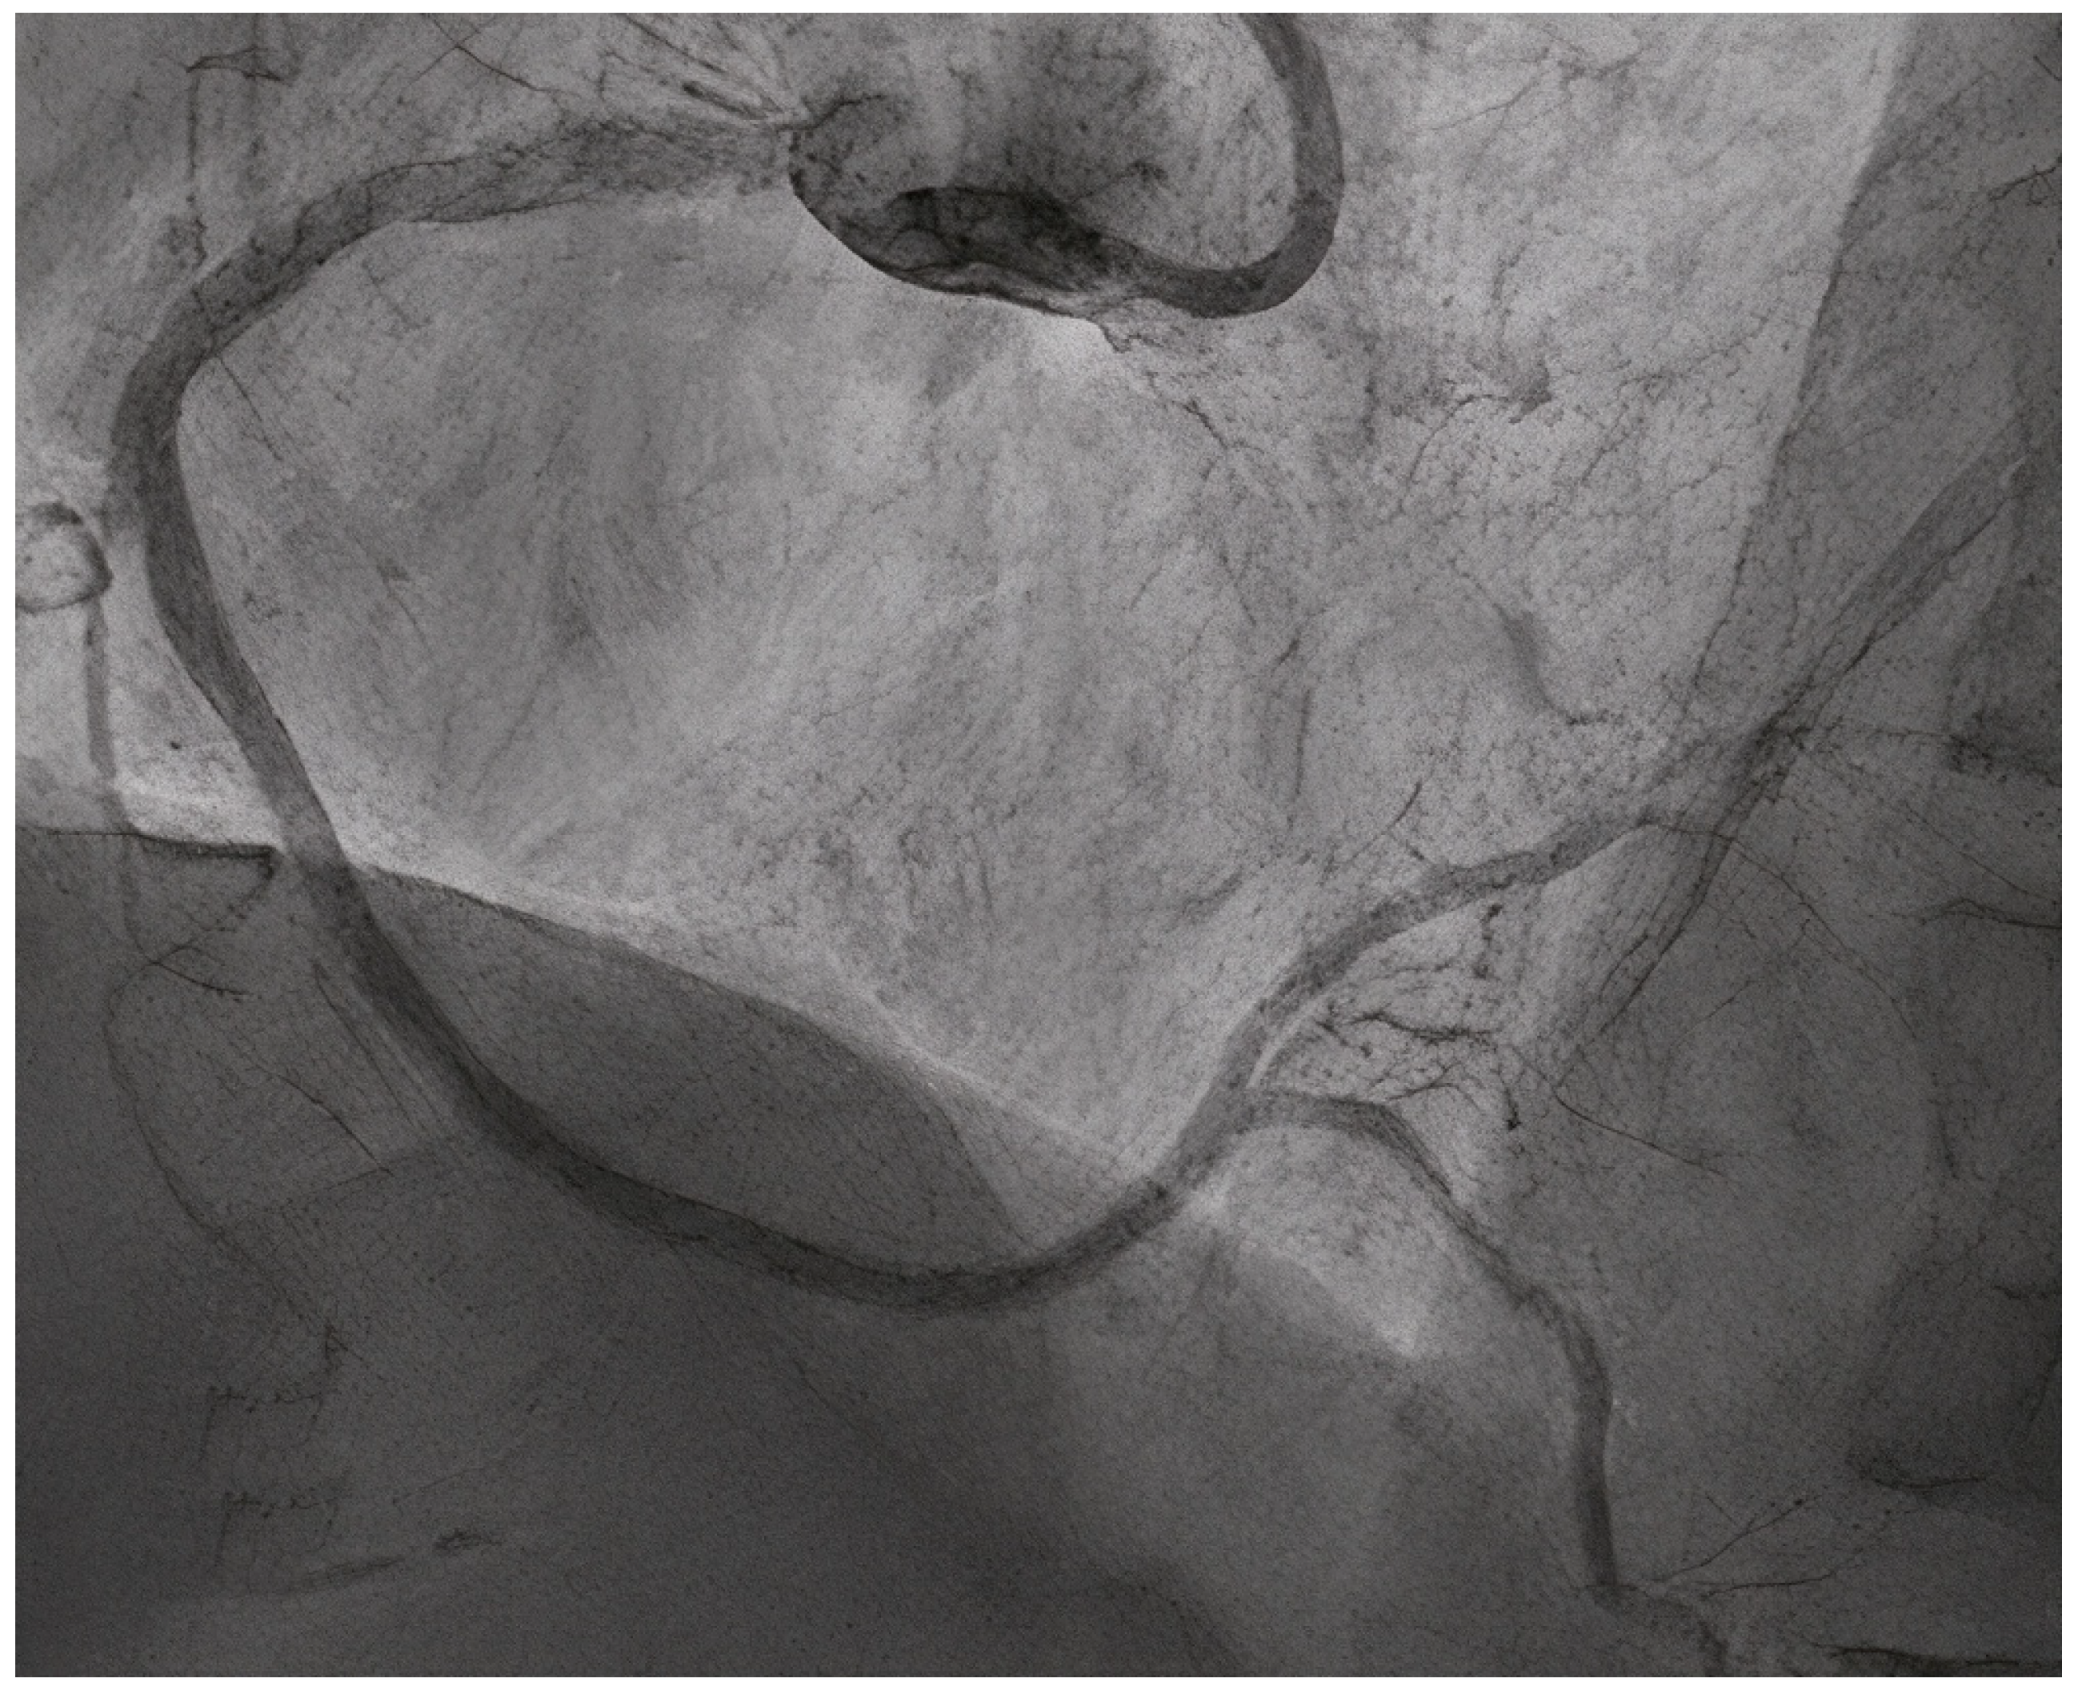

- Uskela, S.; Eranti, A.; Kärkkäinen, J.M.; Rissanen, T.T. Drug-coated balloon-only strategy for percutaneous coronary intervention of de novo left main coronary artery disease: The importance of proper lesion preparation. Front. Med. 2023, 17, 75–84. [Google Scholar] [CrossRef]